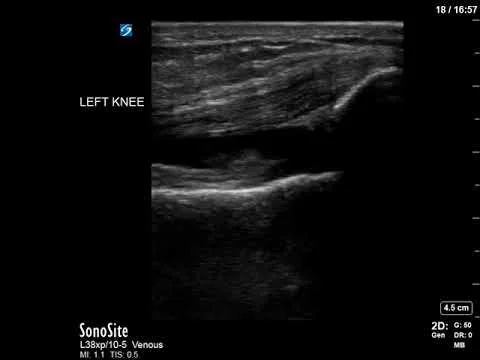

Knee effusion

Small left knee effusion